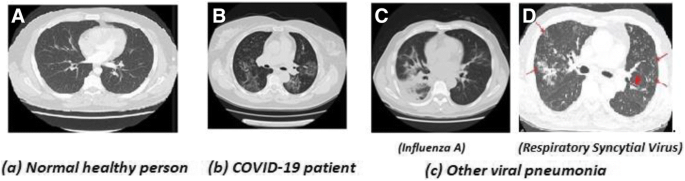

Entropy Free Full Text Classification Of Covid 19 Coronavirus Pneumonia And Healthy Lungs In Ct Scans Using Q Deformed Entropy And Deep Learning Features